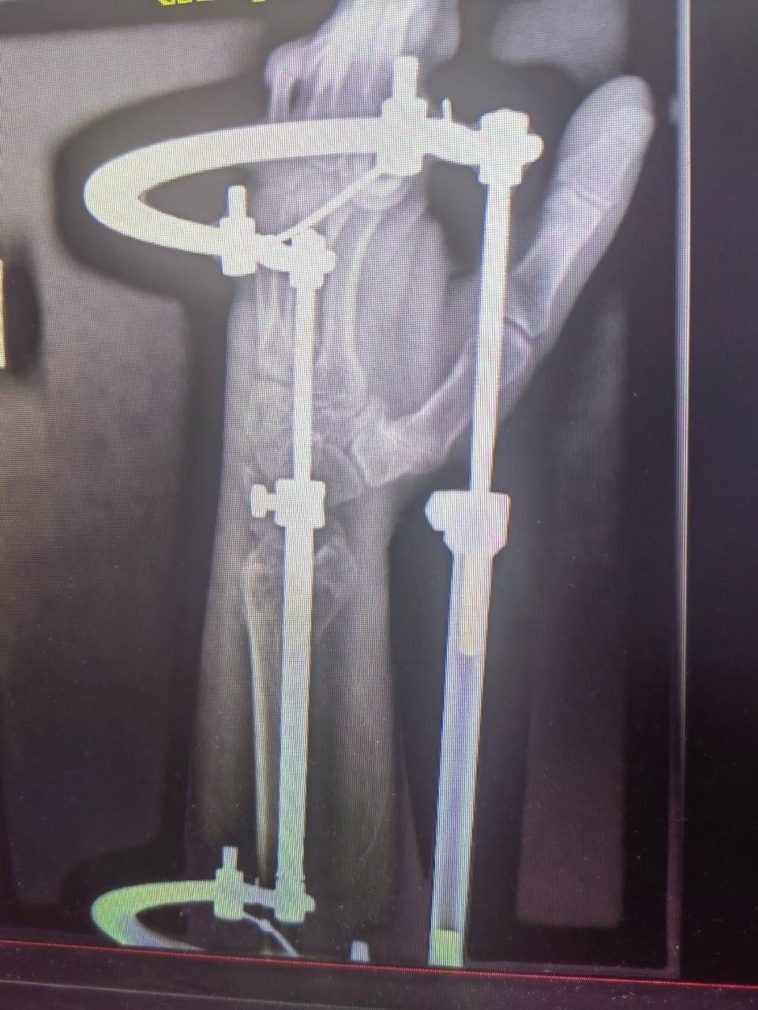

Фото: пресс-служба больницы скорой медицинской помощи Ставрополя Кира Лютова

Врачи провели остеосинтез правой локтевой кости и репозицию левой лучевой кости. Параллельно с пациентом работали неврологи. Терапевт помог справиться с осложнением — токсическим гепатитом.